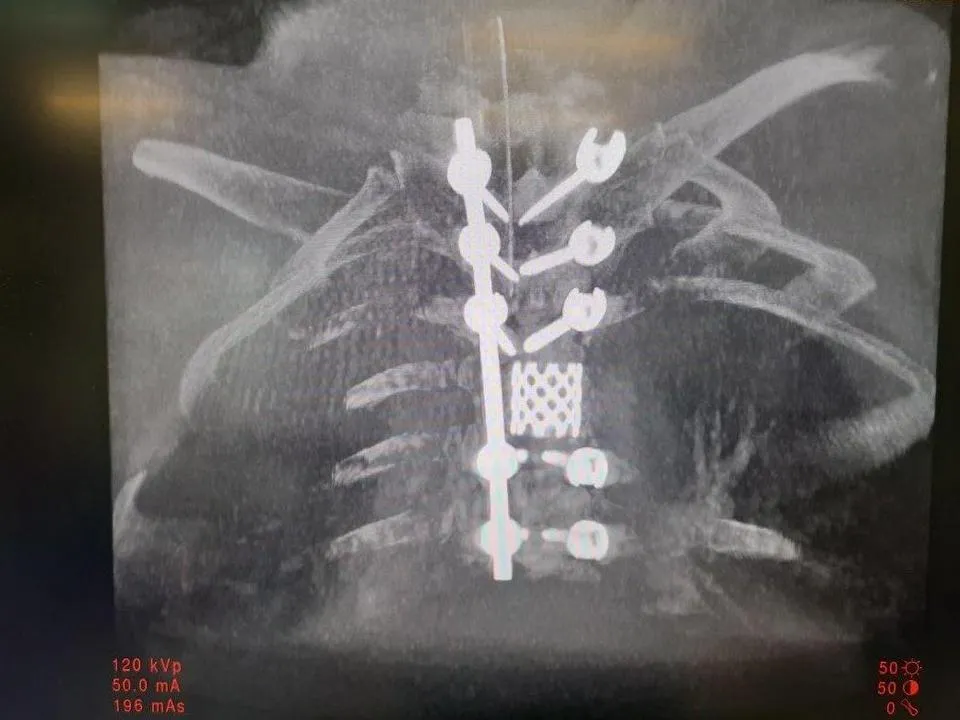

Нейрохирургическое отделение в больнице – одно из самых молодых. 16 сентября оно отметило пятилетний юбилей. Мытищинские нейрохирурги планово и экстренно оперируют не только жителей округа, но и пациентов из других муниципалитетов. В отделение поступают люди с заболеваниями нервной системы, черепно-мозговыми и позвоночно-спинальными травмами, геморрагическими и ишемическими инсультами. Специалисты оперируют грыжи межпозвоночного диска всех отделов.